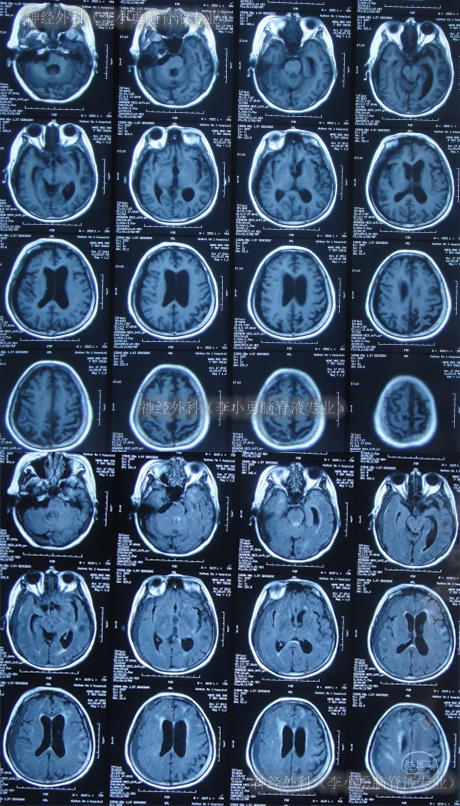

又过2月后即2011年10月14日,夜里2点起夜时突然站不稳,再次出现头昏,呕吐频繁,四肢无力,2011年10月17日第2次就诊于第2家医院:呼和浩特市某医院神经内科住院治疗,行头颅MRI(图-1)认为“末梢神经脱髓鞘病变,考虑为格林巴利综合征,轻度脑积水”。

图-1:2011年11月17日头颅核磁